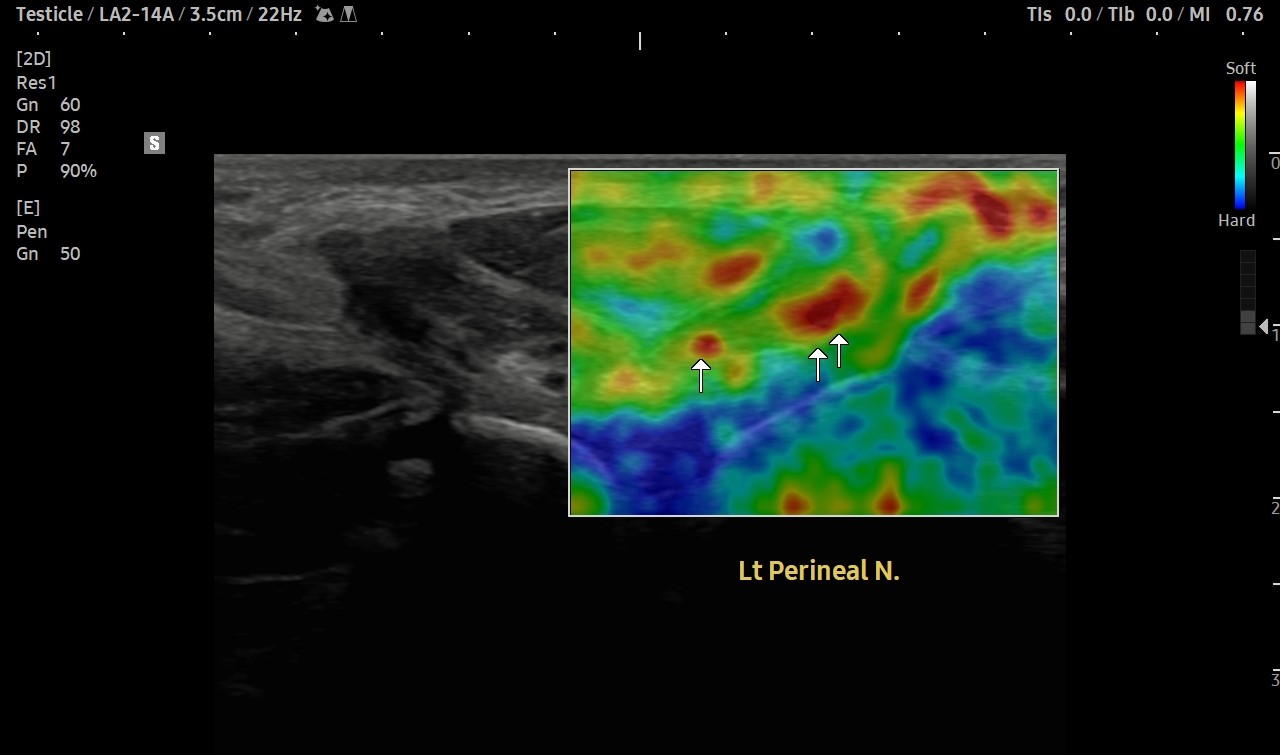

[치료 전]

[치료 후]

- 치료횟수 : 30 회